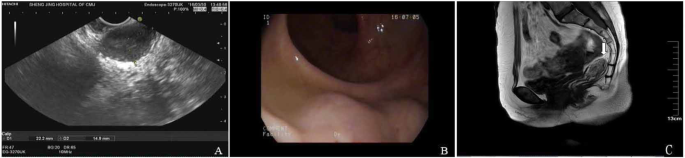

We reviewed the relative cases in Shengjing Hospital during 2001–2018. The other GIST patient, a 69-year-old woman with hypertension, was also treated with transvaginal resection. The tumor was 4 cm in diameter, was located in the vaginal-rectal space and protruded from the lower posterior vaginal wall. On gynecological examination, we found that the mass was fixed and closely attached to the vaginal wall. The results of endoscopic ultrasonography showed that only a small portion of the tumor protruded from the anterior rectal wall (Fig. 4a). Colonoscopy revealed that the root of the tumor was located approximately 3 cm above the dentate line (Fig. 4b). The results of pelvic MR imaging showed that the tumor was located in the space of the rectovaginal septum and encapsulated by the rectal muscle, with partially unclear boundary to the vaginal wall (Fig. 4c). The ultrasound biopsy showed that some spindle-shaped cells were irregularly arranged. The cells were stained positive for CD117 and Dog-1 (Fig. 5). The results suggested a low–moderate risk rectal GIST. The patient also refused to radical surgery for her old age and possible anal dysfunction. We suggested the patient consider preoperative imatinib treatment, since it may reduce the tumor volume and improve the chances of radical surgery. However, the patient refused preoperative imatinib treatment. At last, we chose a transvaginal resection as an alternative. The surgical method was similar to that described in the previous case (Fig. 6a). During surgery, we found the tumor was a circumscribed rectal submucosal mass with vaginal submucosa invasion. The tumor was intactly excised with the adherent vaginal wall and the rectal mucosa showed only a 2 × 1.5 cm2 defect. We repaired the defect and stitched all the layers (Fig. 6b). The postoperative course was safe and quick. The patient went back home on the fifth day without any anal dysfunction nor vaginal-rectal fistula. The results of postoperative histological examination showed that the tumor was resected with clear margin (Fig. 6c). They were coherent with the results of preoperative biopsy. The patient recovered quickly. She had not suffered any anal dysfunction nor postoperative vaginal-rectal fistula. She also refused radical resection but received imatinib treatment after surgery. She remained tumor-free for 12 months till now.

Imaging examination shows the location of the other rectal GIST. a Endoscopic ultrasonography shows that the tumor protruded from the anterior rectal wall. b The colonoscopy results show that the root of the tumor was located only 3 cm above the dentate line. c The results of MR (arrow) showed that the tumor was located in the space of the rectovaginal septum and encapsulated by the rectal muscle, with partially unclear boundary to the vaginal wall